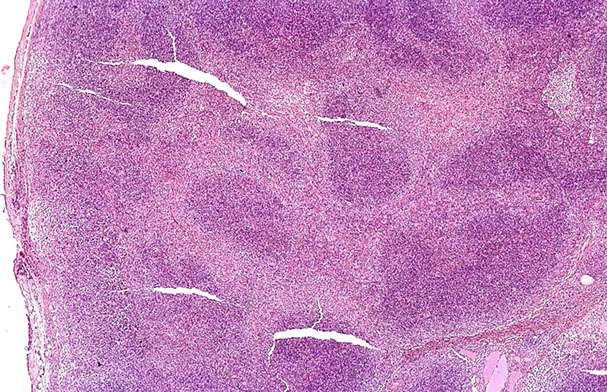

Micro: LN c diffuse nodal involvement showing pseudofollicular architecture (no true mantle zone) c large pale prolif centers c prolymphocytes (>11%; sm to med size cells c clumped chromatin and small nucleoli), paraimmunoblasts (larger, c round to oval nuclei, central red nucleoli)

CLL/SLL can have a perifollicular and/or follicular growth pattern

CLL, proliferation centers (pseudofollicles), usually MUM1+

from LASOP lecture, 1/18/2020

CLL pseudofollicle (proliferation center). Little lymphocytes with small cytoplasm on the left. On the right, paraimmunoblasts are larger, with a little more cytoplasm, with prolymphocytes (black arrow)showing dispersed chromatin, and the red arrow to paraimmunoblasts with prominent central nucleolus (called "paraimmunoblasts" because typically smaller than B-type immunoblasts).

LASOP lecture Dr Reichard, 1/18/2020

"Accelerated" CLL, with Ki67 >40% in proliferation centers can have  px bwt CLL and DLBCL

The "MZ look" found in some cases of CLL/SLL, looks like proliferation centers surround germinal centers

CLL/SLL can show nuclear irregularity

CLL IHC. CD20 (upper left), CD3 strangely highlighting some of the GCs (upper right), CD5 (lower left) shows staining of at least a few of the B-cells, and CD43 (lower right) is positive on many of the B-cells and shows a small ring of negative cells .  around the proliferation center in mantle zone area (black arrow)

Ki67 Showing a small ring around proliferation centers in mantle zone area (same case as IHC to the left)

CLL/SLL IHC. Follicular dendritic cells and neoplastic B cells are positive for CD23 (upper right), the FDCs and B-cells are strongly positive for IgM (upper right), and are Kappa-restiricted (bottom images)

CD279/PD1 T-cells strongly + in Germinal Centers (GC)

CLL IHC. CD3 positive (upper left), LEF1 staining a subset of B-cells (upper right), IgD weakly positive in the tumor cells and more strongly (darker) positive in the residual mantle zone (bottom left), with LEF1 negative in the mantle zone (bottom right)

CLL IHC. In this case, MUM1 with weaker staining on some B-cells and was strongly positive in some areas(upper image), Ki67 showing more positivity in the germinal center-like areas, less positivity in the mantle-cell areas, and then moderate proliferation in the interfollicular areas (bottom image)

MYC more strongly positive in proliferation center-like areas